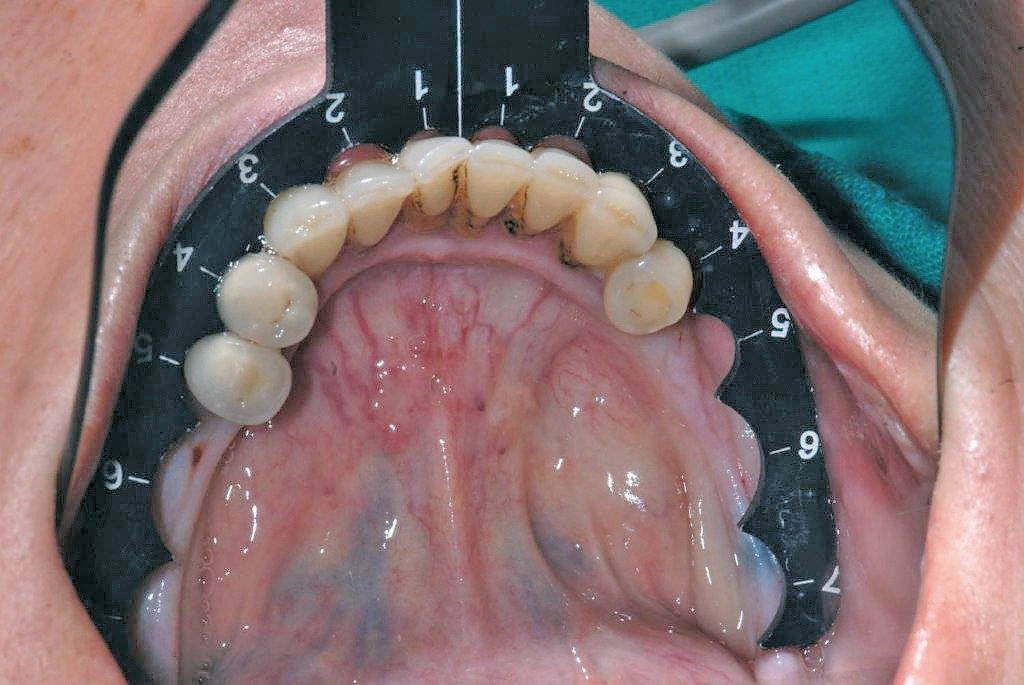

10) MIMI-Navigation: Beim MIMI-Verfahren bedienen wir uns einerseits der CNIP-Navigation (sagittale Navigation) und andererseits prothetischer Schablonen (mesial/distal orientierte Navigation), die für den Unter- und Oberkiefer immer wieder benutz-, sterilisier- und einsetzbar sind: Diese von Prof. Dr. A. El-Hamid (Casablanca) entwickelten Schablonen sind wirklich praktisch in der Handhabung: Man formt die Schablone extraoral entsprechend des Kieferkamms, legt sie am jeweiligen Kiefer an und erhält auf diese Weise die bestmögliche prothetische Position der zu inserierenden Implantate mit jeweils ausreichenden intraimplantären Abständen (Abb. 14). Die sagittal ausgerichtete CNIP-Navigation begleitet die Champions- Guides! Vergleichen kann man CNIP mit der Handaufbereitung von Wurzelkanälen bei einer Endodontie- Behandlung, bei der auch kein Kanal auf diese Weise perforiert werden kann. Analog des „weichen“ Nervkanals lassen die kompakten Außenwände (bukkal und oral) die konischen Dreikantbohrer nur in der „weichen“ Spongiosa des Knochens arbeiten, in die Tiefe gelangen und Kavitäten aufbereiten. Alle Bohrungen werden nur mit konischen Dreikantbohrern und 50–70 U/Min in der Spongiosa durchgeführt. Eine Perforation nach bukkal oder oral ist mit diesen Instrumenten bei diesen niedrigen Touren und deshalb auch mit Implantaten gänzlich ausgeschlossen! Dies gilt auch bei MIMI II-Behandlungen (Distraktion von schmalen Kieferkämmen ohne Mukoperiostlappen-Bildungen) (Abb. 15).